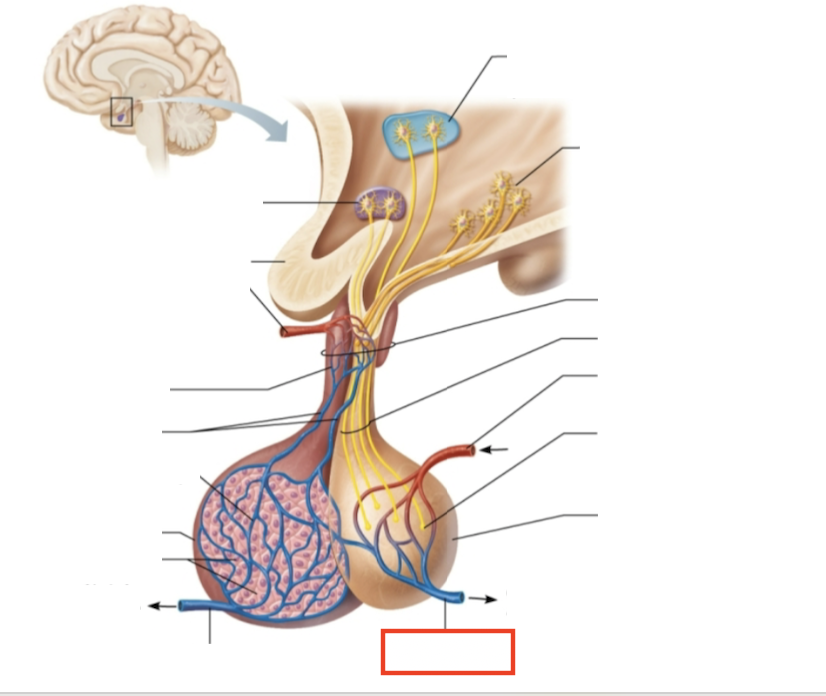

What structure is highlighted?

testes (male)

What are the target organs and effects of testosterone?

most cells of the body; promotes the maturation of the male reproductive organs, the development of secondary sex characteristics, sperm production, and sex drive

What hormone is produced by the testes?

testosterone

What stimulates testosterone production?

LH and FSH